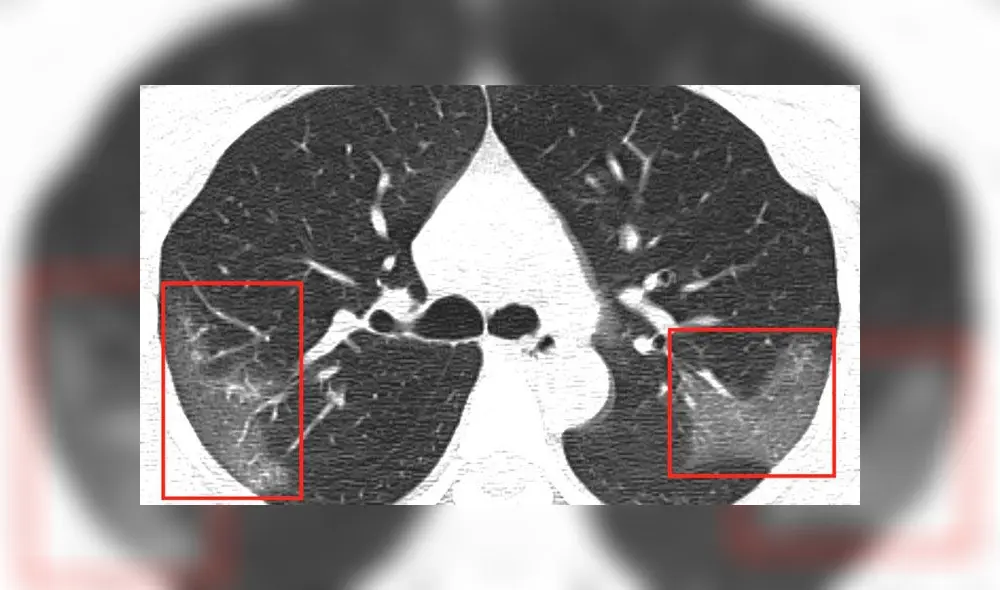

Evolución de las manchas en los pulmones después de tres días. Imagen: First Hospital of Lanzhou University.

En la primera radiografía, los médicos detectaron unas manchas blancas en la esquina inferior de los pulmones de la paciente, que se mantiene en el anonimato. Los expertos comparan la tonalidad de las manchas con la “opacidad de vidrio esmerilado”.

Sin embargo, las manchas se extendían hasta los bordes de los pulmones de la mujer, lo que antes también se había detectado en los infectados por coronavirus como el SARS y MERS.

Luego de tres días de tratamiento, los médicos realizaron nuevas radiografías para descartar un caso de neumonía común. Al ver las imágenes, se percataron de que las manchas blancas eran más notorias y extensas.